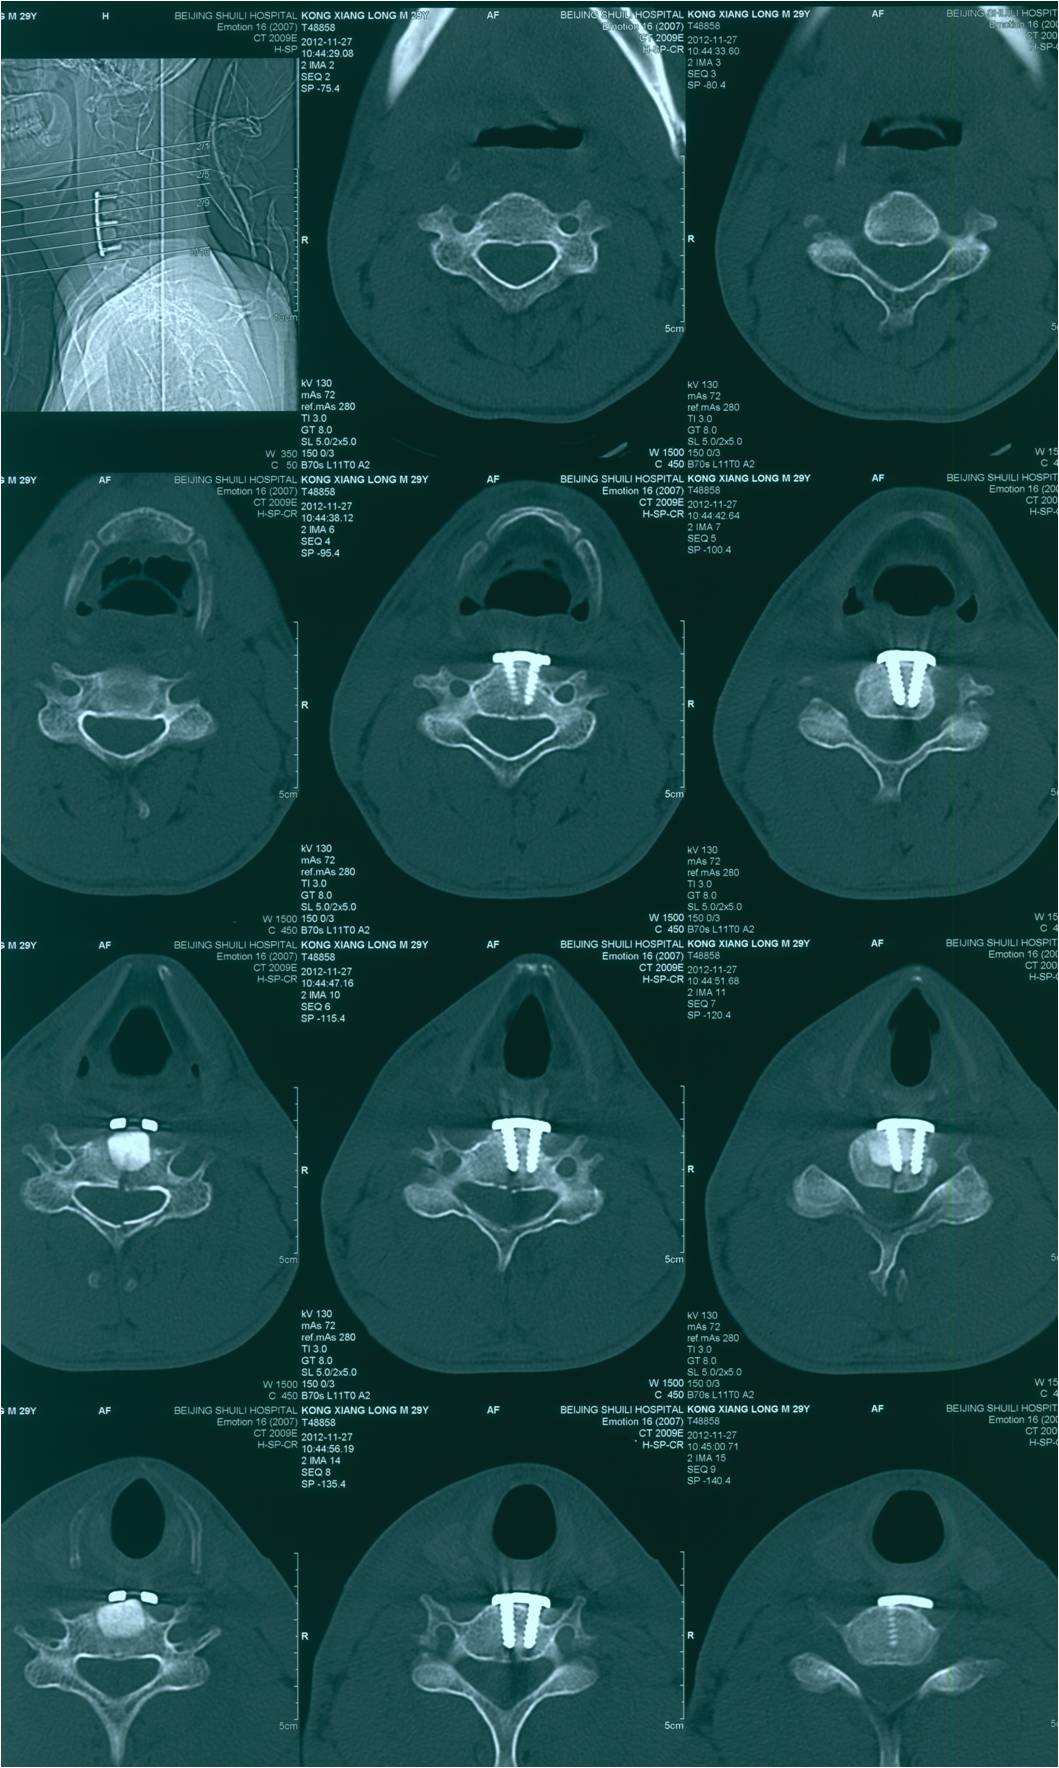

2012-11-18 车祸致四肢感觉、运动及二便功能障碍。

查体:意识清楚,呼吸均匀,查体合作。双侧感觉平面颈4,运动平面颈5. 颈6以下轻触觉保留至肛周,针刺觉消失。颈5以下只有肛门括约肌保留运动功能。下肢肌张力0级。腱反射消失。球海绵体反射可引出。当地医院行X片、CT、MRI检查